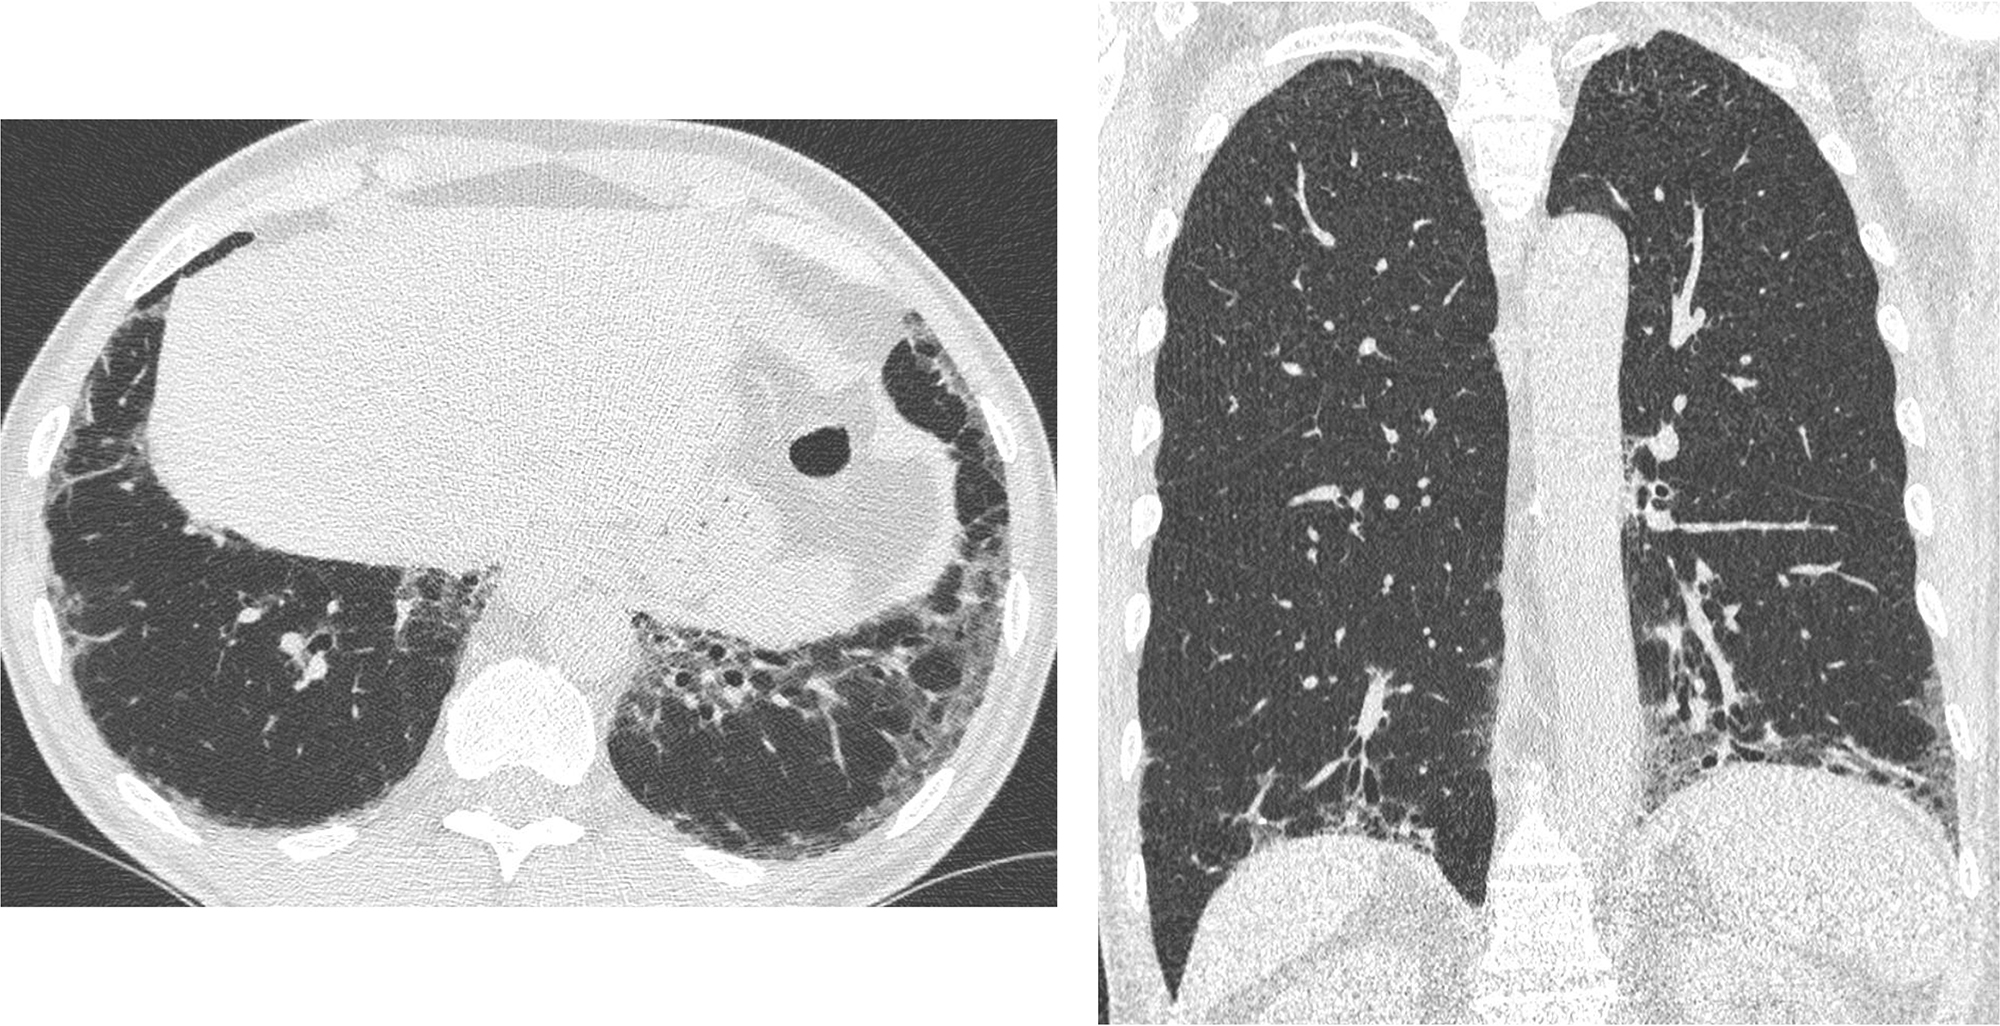

PO:10:141 | A Case Study: Navigating the VEXAS Syndrome Mimickers

Erika Montabone1, Richard Borrelli1, Nicolò Rashidy1, Fabiana Giannoccaro2, Giuseppe Guida2, Federico Itri3, Renato Carignola4, Simone Negrini1, Stefania Nicola1, Luca Lo Sardo1, Iuliana Badiu1, Federica Corradi1, Ambra Bonvicino5, Maurizio Balbi6, Luisa Brussino1 | 1SCDU Immunologia e Allergologia, AO Mauriziano, Dipartimento di Scienze Mediche, Università degli Studi di Torino Torino, Italy; 2SSD Asma grave, malattie rare del polmone e fisiopatologia respiratoria, AOU San Luigi Gonzaga Orbassano, Italy; 3SCDU Medicina Interna ad indirizzo Ematologico, AOU San Luigi Gonzaga Orbassano, Italy; 4SCDU Medicina Interna, Scleroderma Unit, AOU San Luigi Gonzaga Orbassano, Italy; 5SCDU Dermatologia, Città della Salute e della Scienza di Torino Torino, Italy; 6SCDU Radiodiagnostica, AOU San Luigi Gonzaga, Dipartimento di Oncologia Orbassano, Italy